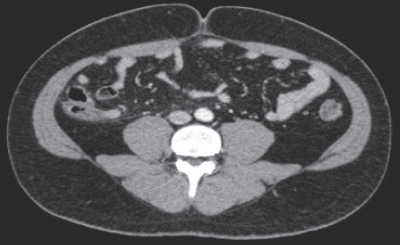

血液所見:赤血球486万、Hb 15.2g/dL、Ht 43%、白血球16,200、血小板24万。血液生化学所見:総蛋白6.4g/dL、アルブミン4.2g/dL、総ビリルビン0.7mg/dL、AST 23U/L、ALT 18U/L、LD 147U/L(基準120~245)、尿素窒素20mg/dL、クレアチニン0.9mg/dL。CRP 0.9mg/dL。腹部超音波検査では病変の描出が不明瞭であった。腹部造影CTの横断像と斜冠状断像を別に示す。